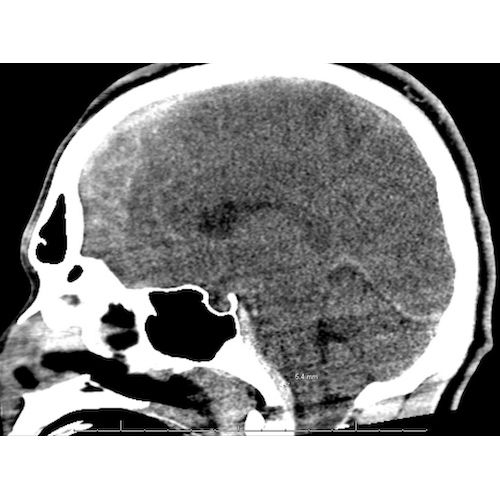

| A Fellow's Role In Multiteam Coordination For Severe Brain Injury Management In Football - Page #3 | |||